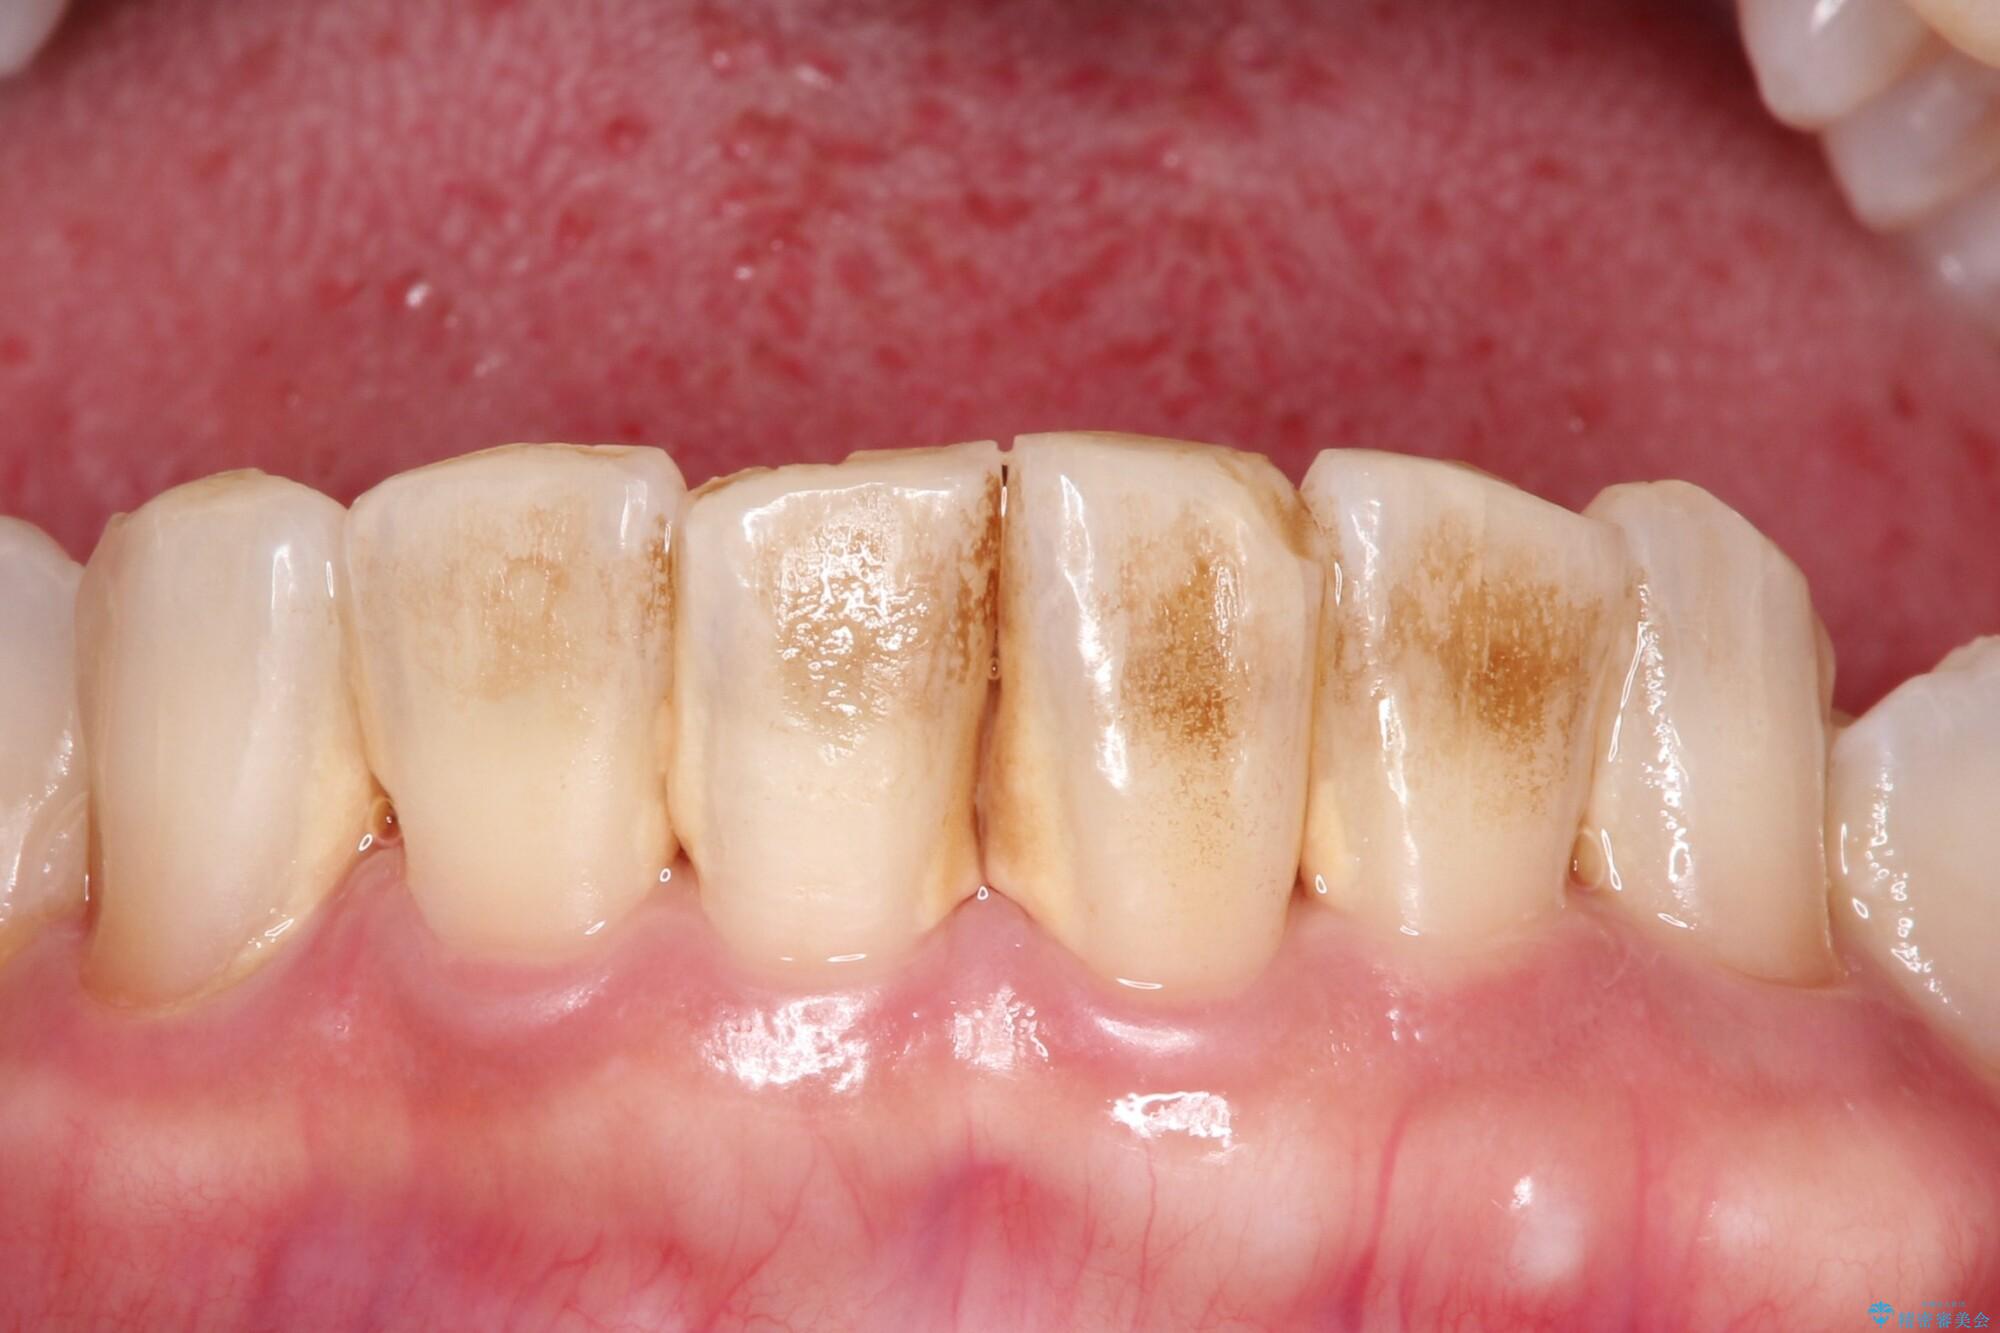

- 久々のクリーニングで来院されました。歯の表面のステイン付着と、下顎前歯に歯石がみられました。今回はPMTCをおすすめしました。

ステインを除去したことで全体のトーンが明るくなりました。下顎前歯は歯石で埋まってしまっていたため、クリーニング後はスペースができたように見えますが、歯本来の形へ戻りました。